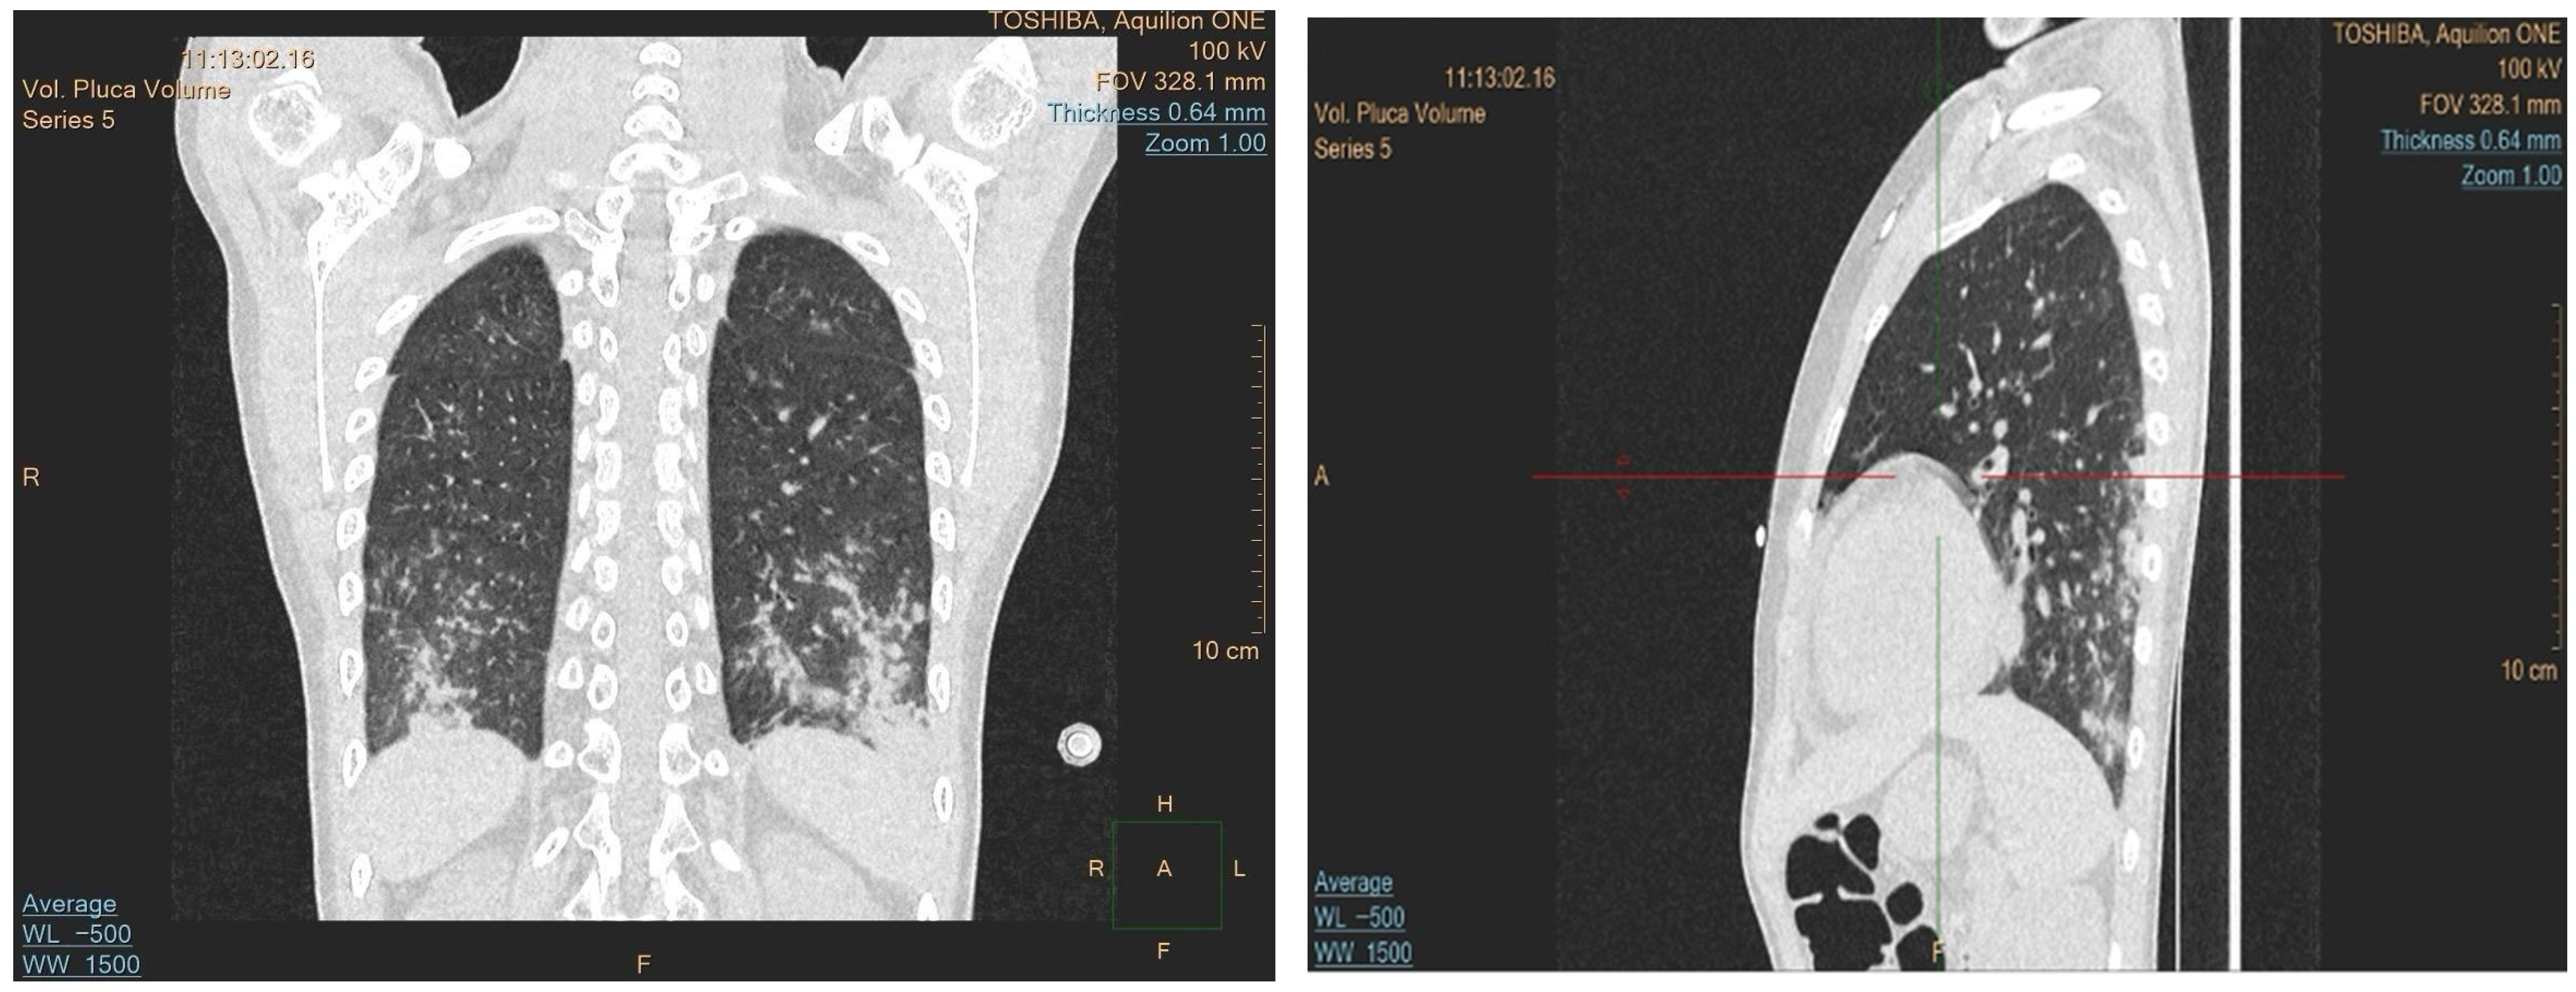

A 10-year-old boy presented to the hospital with easy bruising, exercise intolerance, and a fever. He had had a prior cytomegalovirus infection and was admitted due to persistent abnormal blood counts. A physical exam showed pallor, petechiae, and bruises on his lower extremities and right elbow. Initial blood morphology tests showed a hemoglobin level of 5.1 g/dL (10–15.5 g/dL), 4.2 × 109/L leukocytes (4.5–13.5 × 109/L), 82 × 109/L platelets (150–450 × 109/L), and a neutrophil count of 0.64 × 109/L (1.4–6.1 × 109/L), indicating pancytopenia. Bone marrow aspiration was inconclusive due to severe artifacts. Although insufficient for a definitive morphological diagnosis, the smear showed occasional blast cells with cytoplasmic protrusions suggestive of megakaryoblastic differentiation (Figure 1); therefore, a trephine biopsy was performed. It showed hypocellular marrow (30–40%) with fibrosis, a reduced myeloid lineage, dysplastic megakaryocytes, and 10% weak CD34+ cells, suggesting myelodysplastic syndrome. Following the trephine biopsy, a histopathological and immunophenotypic analysis of the bone marrow was performed due to a suspicion of MDS, which confirmed AMKL, with CD61 positivity on numerous dysplastic megakaryocytes and CD71 positivity on the erythroid lineage. Genetic analysis revealed a germline GATA2 mutation and an acquired monosomy 7 in leukemic cells, confirmed by conventional karyotyping and FISH, placing the patient at a high risk. The patient’s family history was significant for maternal GATA2 deficiency; currently in her thirties, the patient’s mother remains asymptomatic. A germline status was inferred from the presence of an identical mutation in the patient’s asymptomatic mother. The mother was not considered a suitable haploidentical donor.

Figure 1. Wright–Giemsa staining of the bone marrow aspirate at a 40× magnification. (A) Platelet aggregation. (B) Lymphocytes. (C) Blast cells with a high nuclear-to-cytoplasmic ratio and cytoplasmic protrusions or “blobs” which resemble platelet budding, which suggests megakaryoblastic differentiation, a characteristic feature of AMKL.